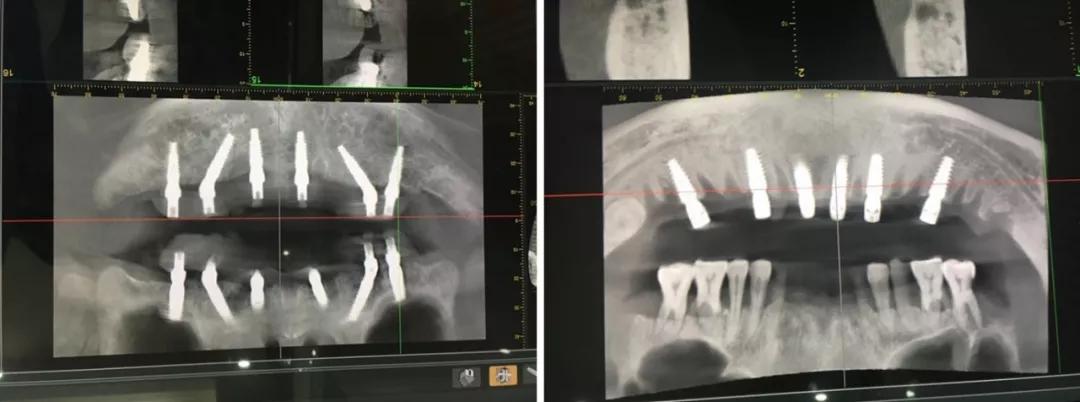

日照口腔医院种植中心配置先进的种植手术室,为患者提供各种类型的种植义齿修复,在日照市最早开展口腔种植技术,采用先进的医疗技术装备和世界一流的种植系统,配备有丹麦3shape口内扫描仪、Yoshida激光治疗仪、卡瓦(KaVo)锥形束CT、超声骨刀等国际先进仪器和设备,装备有瑞士士卓曼等多套国际种植系统,同时配备国际一流的消毒供应室,为疑难复杂病例的诊治提供了必要条件。

医院开展CAD/CAM数字化种植导板技术,通过整合数字化影像、cbct 数据以及数字化加工技术的新型种植导板,充分考虑到了颌骨条件、口腔解剖结构以及修复效果的结合,且精确度高,手术安全性高